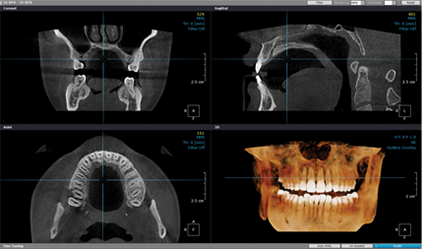

진단 및 치료 계획

파노라마, X-ray, 3D CT 등으로 상태를 면밀하게 진단 후 치료계획을 세웁니다.